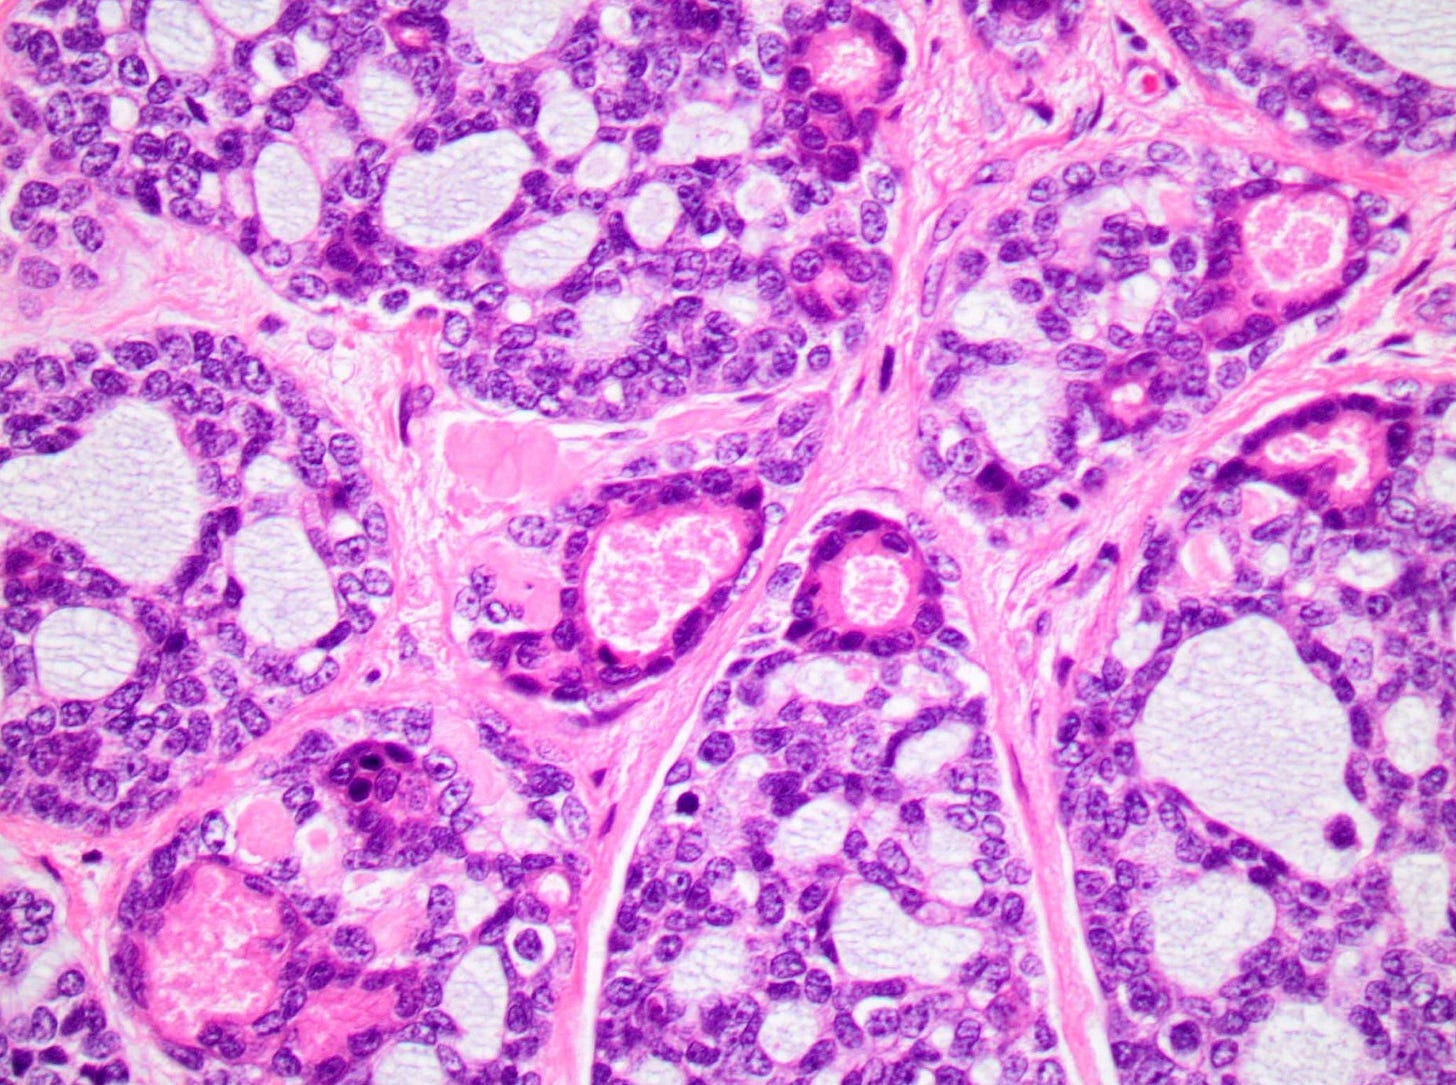

Tall cell carcinoma with reverse polarity - microscopic images

Tall cell carcinoma with reverse polarity presents as a 1 - 3 cm, well circumscribed, firm mass. Microscopically, it is characterized by elongated epithelial cells with abundant glassy eosinophilic cytoplasm and with nuclei located at the apical pole rather than the basal pole, giving the impression of reverse nuclear polarity. Architectural patterns include papillary, tubular and solid formations. In addition, it has papillary thyroid carcinoma features including colloid-like material within luminal spaces, nuclear grooves and overlapping nuclei.